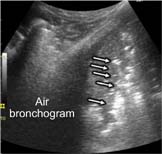

Air bronchogram (Figure 9): sometimes, hyperechoic punctiform images may be seen within the consolidation corresponding to the air-filled bronchi. This is also called air bronchograms. During inspiration, these hyperechoic punctiform images may be reinforced due to penetration of gas into the bronchial tree of the consolidation (the so-called dynamic bronchogram).

FIG 9. Lung consolidation with air bronchogram.